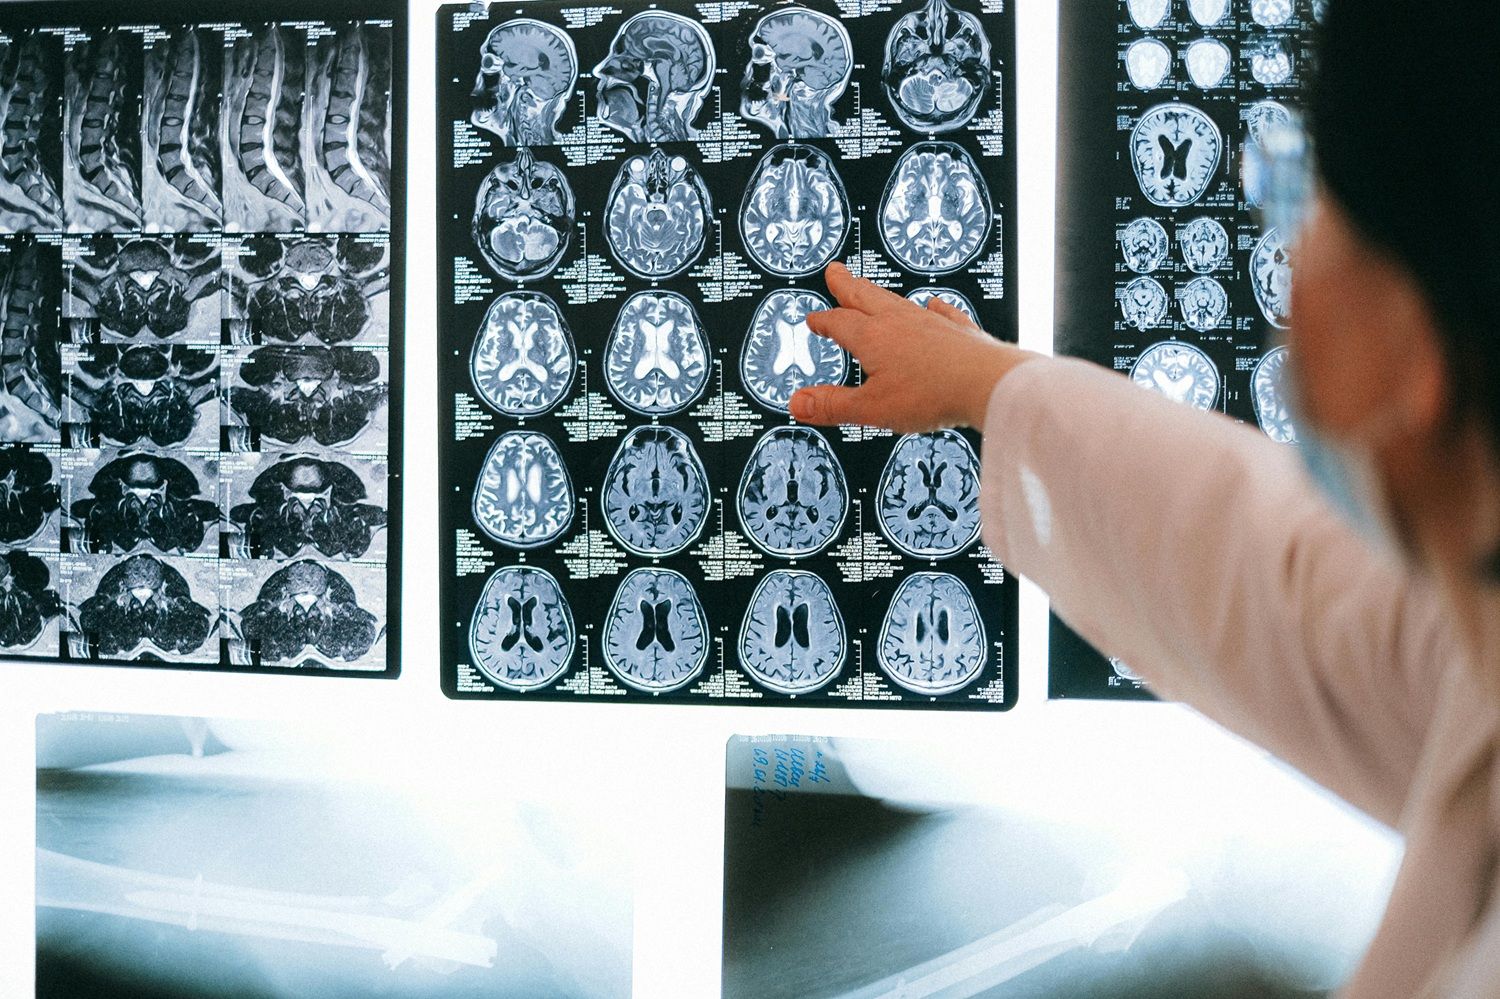

Pesquisas recentes têm aprofundado a compreensão sobre esses efeitos opostos. Um estudo da Universidade do Texas, publicado no Journal of Clinical Medicine em outubro de 2024, mostrou que níveis mais altos de HDL podem ter efeito neuroprotetor. Em exames de imagem realizados com 1.800 adultos, aqueles com mais HDL apresentaram maior volume de matéria cinzenta — o que pode indicar preservação cognitiva ao longo do envelhecimento, inclusive entre pessoas com o gene ApoE4, associado ao Alzheimer.

Na via contrária, uma pesquisa divulgada em julho de 2025 na revista Immunity, conduzida por neurocientistas da Universidade de Purdue, apontou que níveis elevados de LDL entre os 40 e 65 anos aumentam significativamente o risco de Alzheimer e outras demências nas décadas seguintes. O estudo identificou que o excesso de gordura sobrecarrega as microglias — células responsáveis pela defesa e limpeza do cérebro — e faz a enzima lipídica DGAT2 se acumular nessas estruturas, prejudicando a eliminação de placas amiloides.